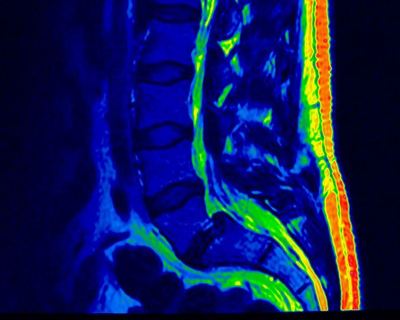

Вообще-то на картинке изображен поясничный отдел, но она покорила меня наглядностью.

И если с ситуацией на последнем рисунке вы мимо врача точно не пройдете, то менее выраженные проблемы могут достаточно долго и упорно отравлять жизнь.

Этот рисунок я выбрал не случайно. Обратите внимание, что суставным отростком позвонка и дужкой может компремироваться спинно-мозговой корешок и будет ситуация очень похожая на радикулопатию при грыже м\п диска, но стандартное лечение будет малоэффективным.